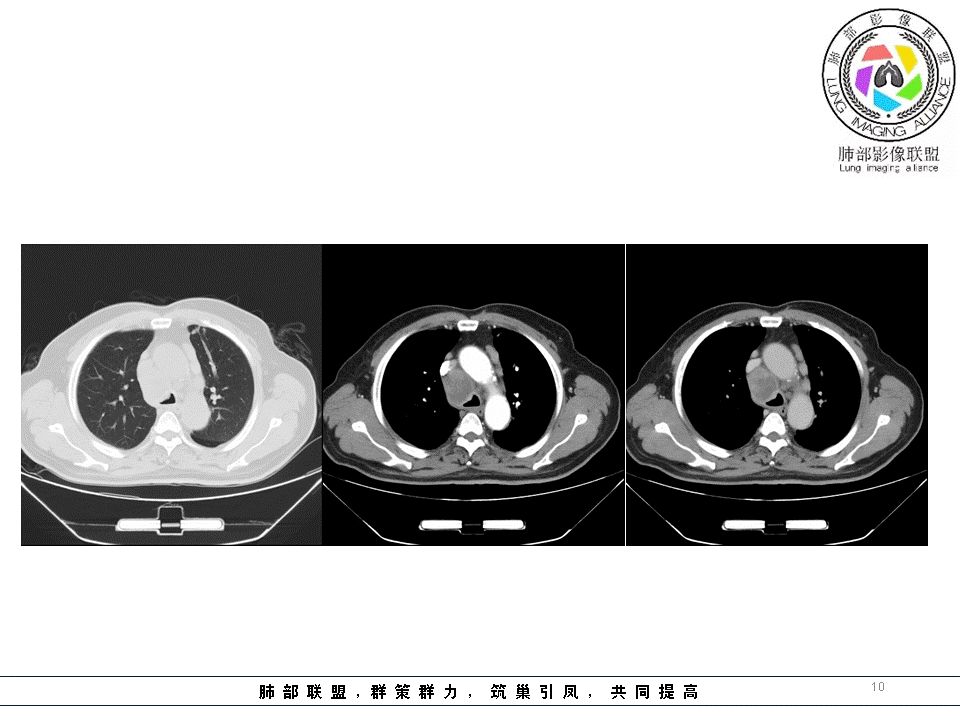

患者,男性,62岁,咳嗽咯痰2月余,半月前CT显示肺间质改变,CT肺窗左上肺斑片结节影,间质性改变,纵隔内多发肿大淋巴结,部分边界清晰,部分融合坏死,分析:1、病史较短,半个月,淋巴结融合坏死,结节病不首先考虑,2、没有冰冻纵隔,肿大淋巴结前纵膈不明显,淋巴瘤、小细胞肺癌转移不考虑,3、CD,一般肿大淋巴结,边界清晰,明显强化,一般无坏死,不考虑,结合临床,病史,纵隔多发淋巴结肿大,部分其内可见坏死低密度,左肺内病灶,气管镜,首先考虑淋巴结结核。

南边:临床:老年男性,病史偏长,2月。临床有通气功能障碍。

南边:但是我们看纵隔就多发的肿大淋巴结,部分融合成团。

南边:而且这些淋巴结,有些直接主要是压迫支气管壁,但是有些是突入到支气管腔内的。可惜我截的图发不上来。就左上舌段,支气管壁明显的增厚。有些明显腔内突的一个结节的,但是远的没有阻塞的特点。南边:增强以后呢,这个病灶明显强化,部分的似乎有环形强化的迹象,但不是很典型。

我们看这个主支气管的层面,主支气管明显受压,有变形的,但是软骨是没有突破的。

结果:肺腺癌并纵膈淋巴结转移

1.临床实践中我们可能会有过多次这样的经验,右锁骨上淋巴结病理肺腺癌,但未能明确原发病灶之所在。该例也是如此,也许在肺叶中瞒天过海,也许隐匿肺门结构间。

3.肺癌淋巴结转移多有一定规律可循。右肺病灶均沿右肺血管束、右肺门、右侧纵隔上行;左肺下叶病灶沿左下肺血管束、左肺门、隆凸及右侧纵隔上行;左肺上叶病灶沿左上肺血管束、左肺门、主动脉窗及左侧纵隔上行。

该例左肺门及腔静脉后淋巴结肿大,是符合这规律的。